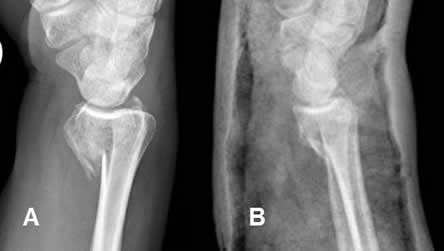

Fig 83. Reducción cerrada.

A: Rx lateral. Fractura del radio distal, con angulación anterior.

B: Rx lateral. Luego de la reducción, se estabiliza con yeso.